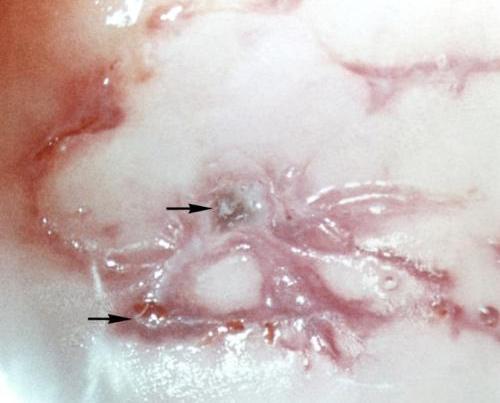

На руках и ногах больных подагрой людей появляются наросты. Эти наросты лопаются через некоторое время, а на месте образования нароста можно увидеть характерный беловатый блеск кристаллов мочевой кислоты, ее уровень в организме значительно повышен. Больные люди чувствуют интенсивную, давящую боль в воспаленных суставах, что мешает вести здоровый образ жизни, полноценно двигаться, выполнять физическую работу. А работа мужчин очень часто связана с физическими нагрузками и двигательной активностью, что приносит ощутимый дискомфорт и болезненные ощущения.

Тофусы — признаки подагры, иначе — подагрические узлы, возникают из-за отложения солей в суставах, организм эти соли воспринимает как инородное тело и старается от них избавиться. Мозг направляет в очаг скопления уратов лейкоциты, чтобы нейтрализовать отложение солей. Происходит сильное воспаление в области сустава и болевое ощущение.